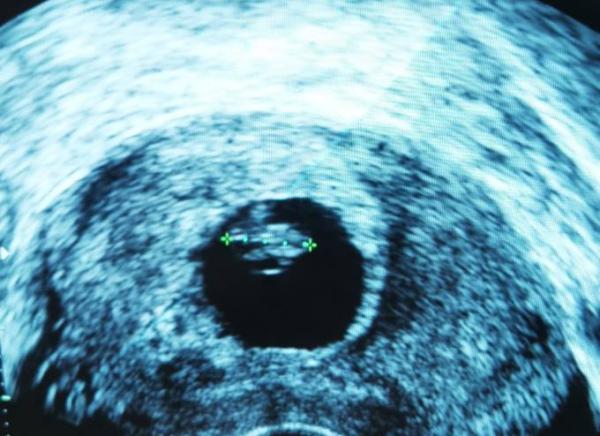

Ich war heute beim Arzt, das Herz hat geschlagen und von der Größe passt es auch.

Danke ihr Lieben!!! Das Würmchen ist jetzt 12mm groß!

Ich dachte er hat 1,7cm gesagt aber das habe ich wohl falsch verstanden, am US Bild steht 1,15... 7+3...